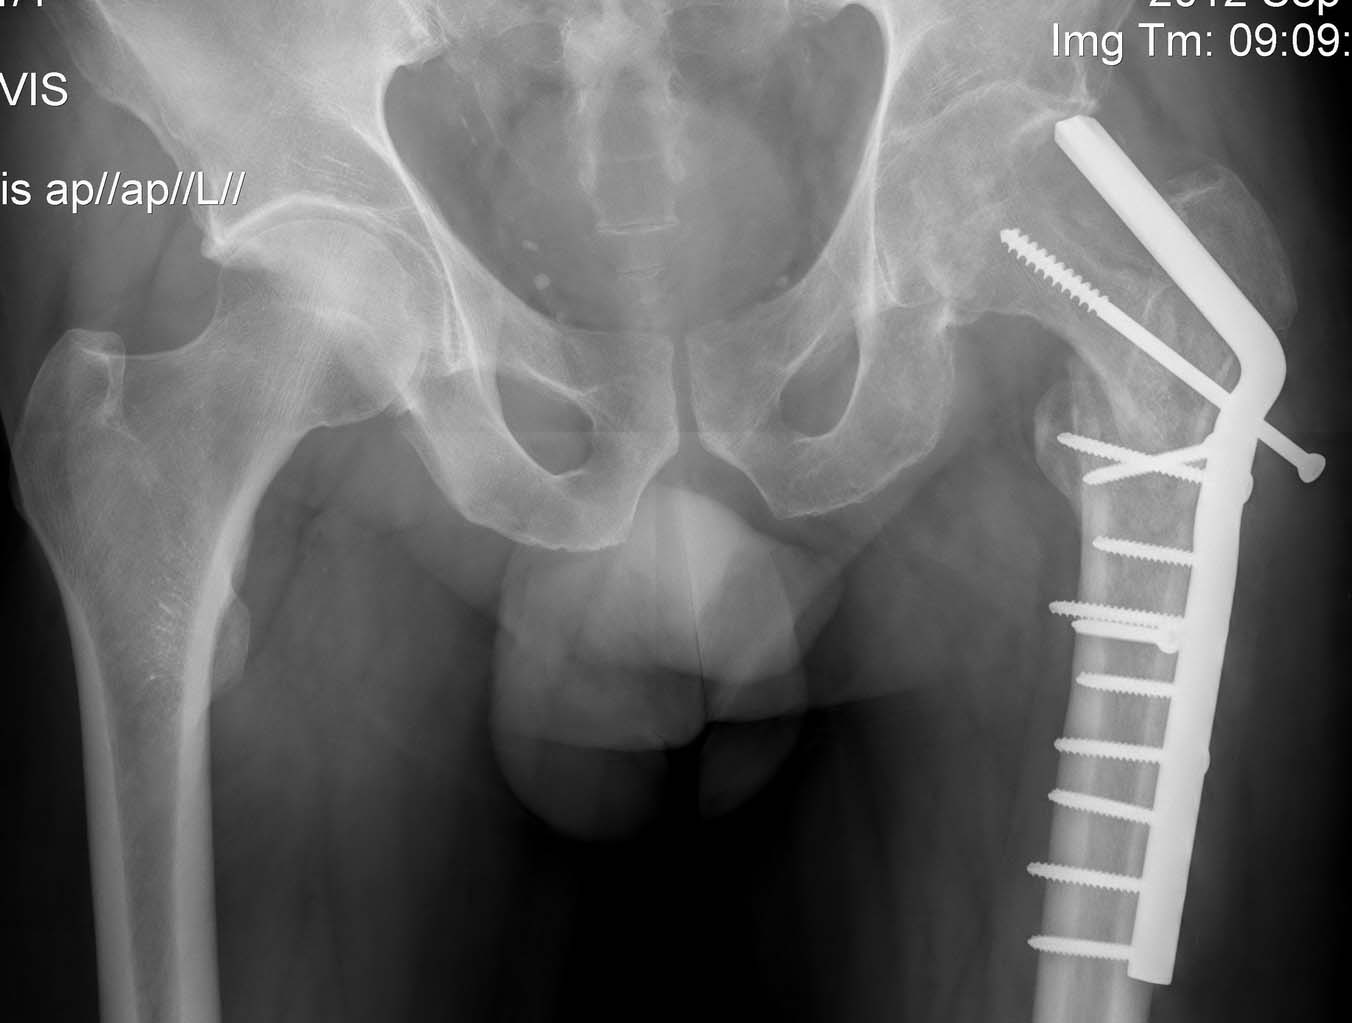

Несращение проксимального отедла бедра, дефект головки

Пациент 55 лет, оперирован клинковой 130 градусной пластиной 6 месяцев назад. После удаления пластины - клинически и рентгенологически несращение.

Хороший пример того, что если сразу не все в порядке, то надеятся на чудо не следует. Пациент 55 лет, оперирован клинковой 130 градусной пластиной 6 месяцев назад (не в нашем ауле:). В надежде на сращение перелома выжидали до 6 месяцев после операции. По предварительным снимкам и КТ было ощущение какой-то консолидации. После удаления пластины - клинически и рентгенологически несращение. На КТ - дефект головки (как и следовало ожидать). Явных признаков инфекции нет. На операции незначительное количество прозрачной "синовиальной" жидкости (взят посев, результат будет через день-два). Не температурит. СОЭ перед операцией 17.

На сегодня беспокоят боли в области несращения, нога не опорна. Рана после удаления фиксатора заживает спокойно (7 дней после операции).

Рентген до, полсе и КТ на сегодняшний день в приложении.

Обсуждается два варианта:

1. Эндопротезирование с отсрочкой месяца на 3.

2. Остеосинтез 95 град клинковой пластиной. Планирую клинком попасть в нижний полюс головки (хотя там тоже плотность кости мала). Для усиления фиксации - спонгиозная пластика канала от клинка старой пластины либо цемент рассасывающийся.

Так как собственного опыта применения биорезобируемых цементов нет, прошу помощи сообщества в совете и выборе оптимального варианта.